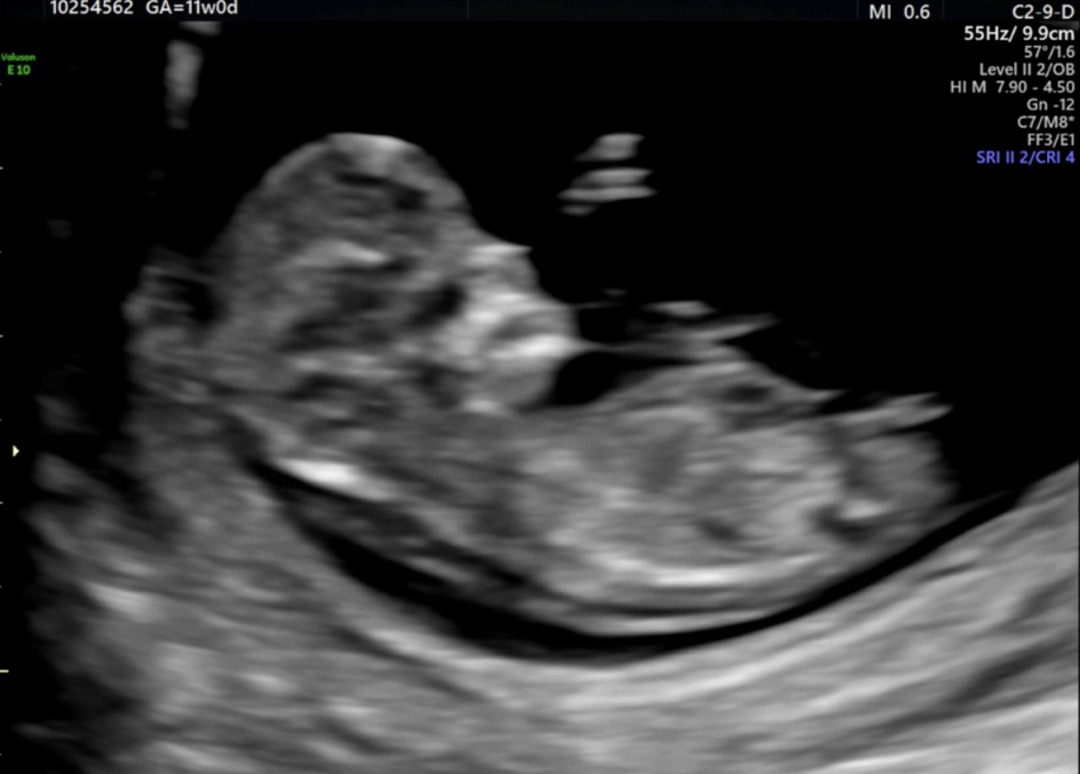

각도법 봐주세요 💓

딸일까요 아들일까요 ? 🥹